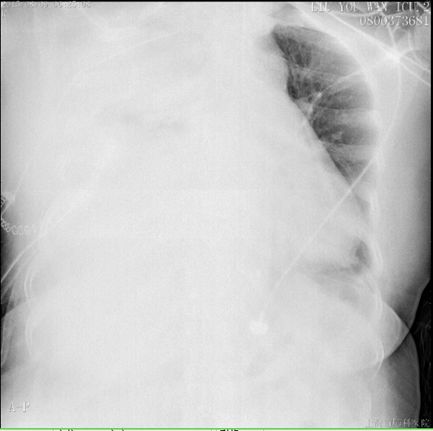

描述:溶栓18h后,胸引量:1700ml

溶栓18h后,胸引量明显增多,同时提醒胸腔内大量血肿,因此于术后第五日,予以全麻下行VATS剖胸止血术,手术时间1.5h,术中失血600ml,输血球2单位,术后带气管插管入ICU。止血术后第一日胸引量450ml,复查血气正常,予以拔除气管插管,SPO2 96%,HR 81bpm,BP 135/88mmHg。